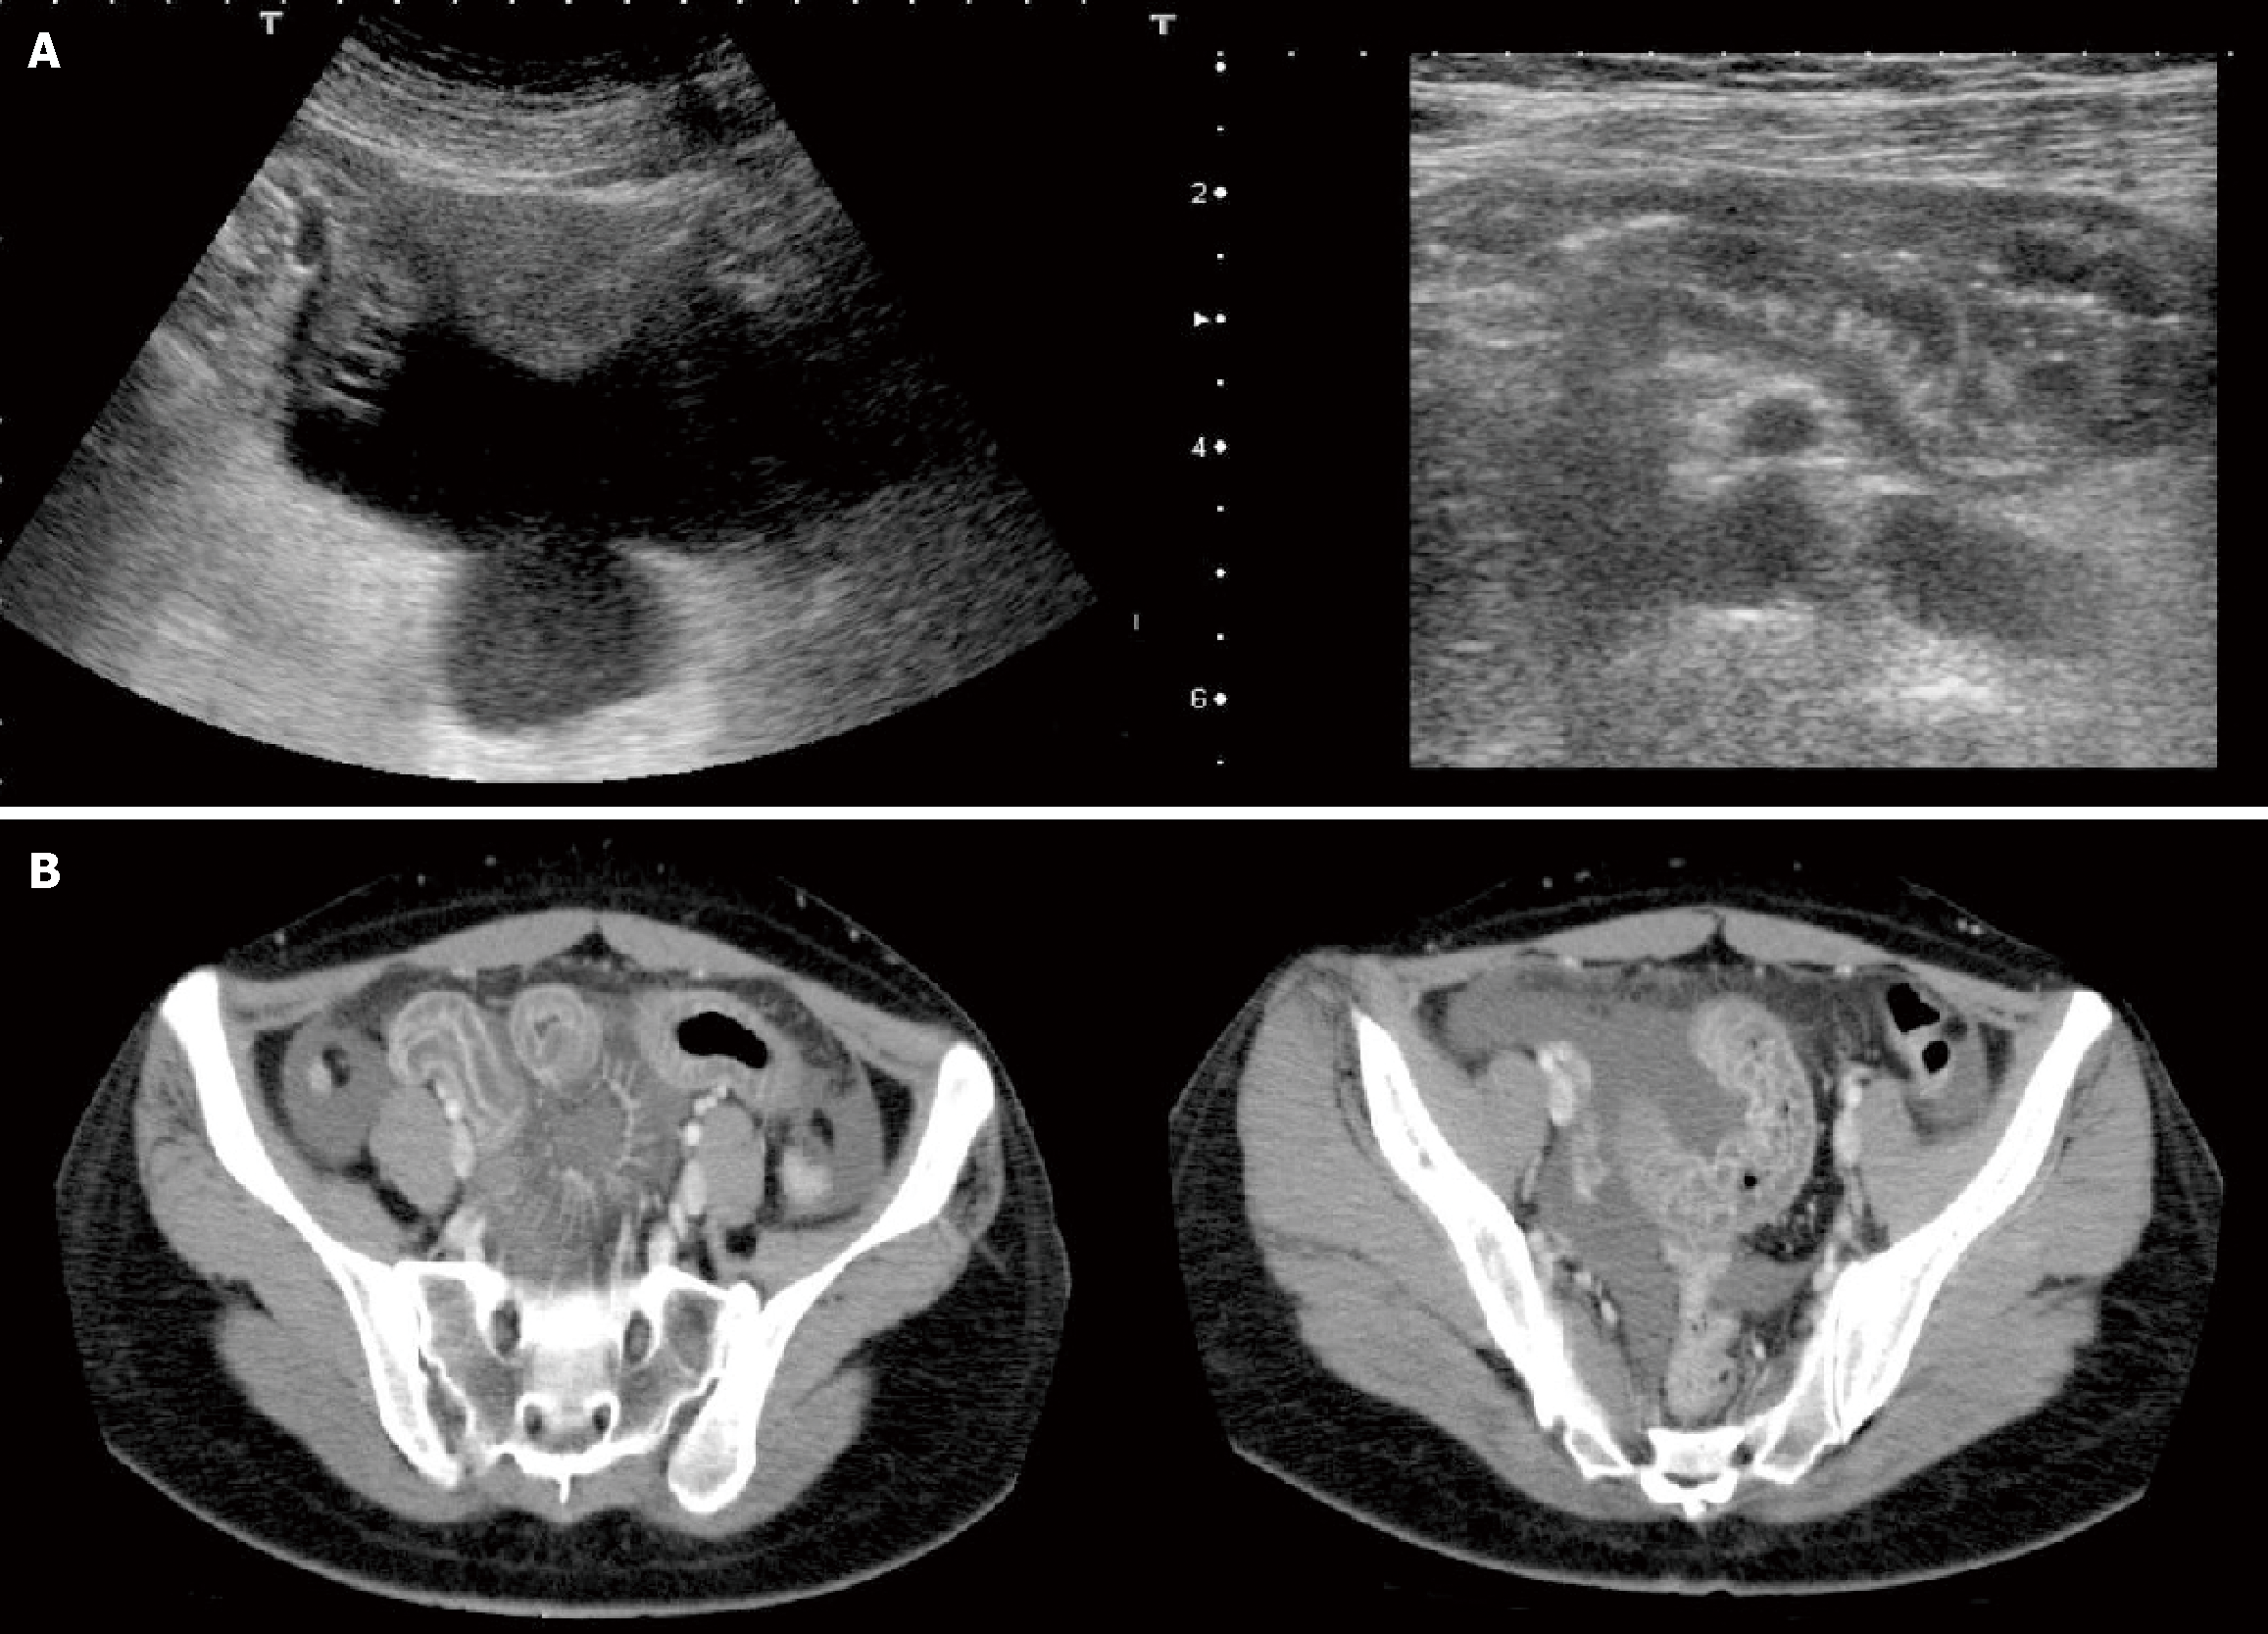

Figure 1 Imaging examinations.

A: Abdominal ultrasound showing significant edema of the pelvic small intestine and ascending colon, and a moderate amount of ascites; B: Abdominal computed tomography scan showing significant edema of the pelvic small intestine and ascending colon, and a moderate amount of ascites.